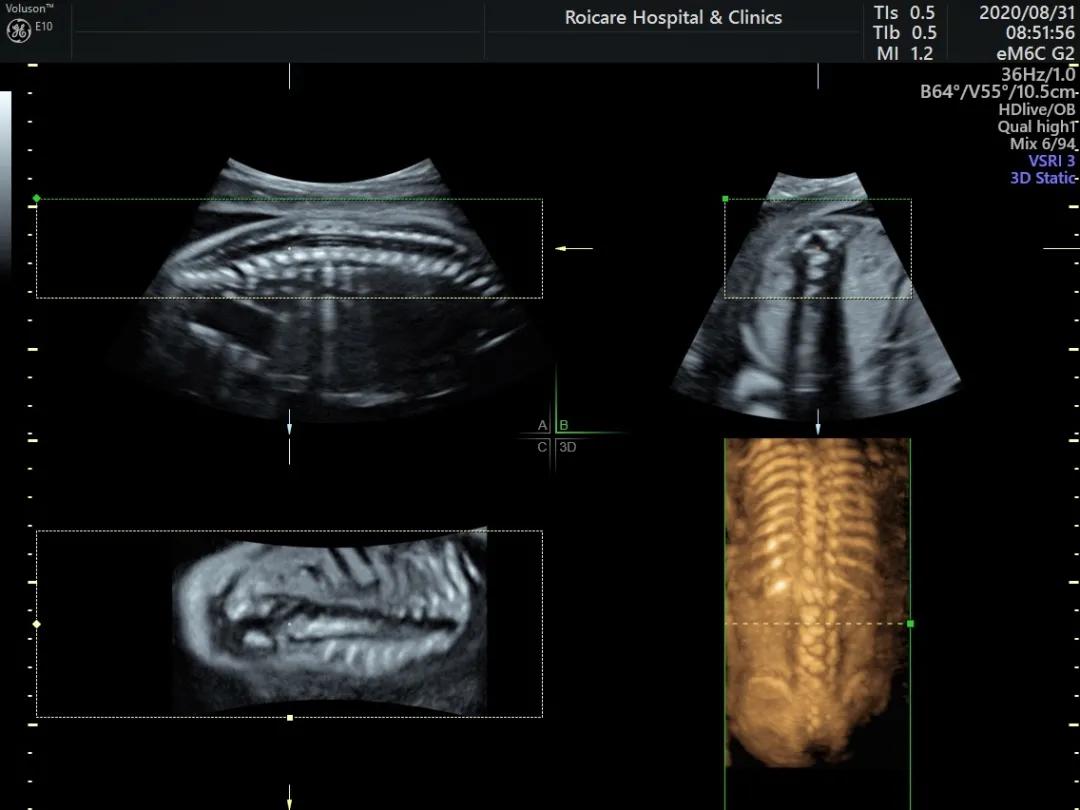

正常位置的脊髓圆锥

出生时脊髓圆锥位于第2腰椎(L2)至第3腰椎(L3)水平,出生后3个月位于L1~L2水平,与成人相同。脊髓下端因各种先天或后天原因受制于椎管的末端不能正常上升,使其位置低于正常,由此而导致的一系列临床神经功能障碍和畸形的综合征即称为脊髓拴系综合征。

正常孕20周以上的胎儿脊髓圆锥的位置达到L3水平以上,如果孕20周以上胎儿脊髓圆锥位置在L4以下,要警惕脊柱裂可能以及是否合并其他异常。中孕期产前超声检查可以发现严重的开放脊柱裂。闭合性脊柱裂表现多样、脊柱裂口小、影像学表现不典型,因此产前超声诊断困难。